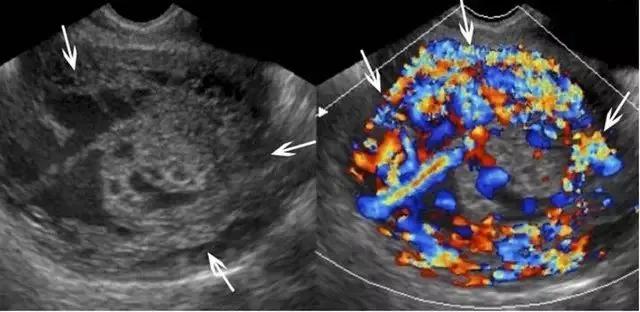

滋养层胎盘肿瘤包括一组源于胎盘滋养组织的相关肿瘤,如部分性及完全性葡萄胎、侵袭性葡萄胎、绒癌、胎盘滋养层肿瘤。引起本病的风险因素包括高龄孕妇与既往患过胎盘滋养层肿瘤病史。部分或完全性葡萄胎是良性病变,部分性葡萄胎伴有胎儿存活,而完全性葡萄胎没有胎儿,其患绒癌的风险性更大。在超声上,葡萄胎的子宫增大,部分性葡萄胎的子宫可见多个弥漫性无回声病变,胎儿因多发先天性畸形、三倍体及生长受限而不能存活(图 16)。

图 16 示部分性葡萄胎:A 为子宫横断面,箭头示宫内不均质囊实性包块,血流丰富,宫内可见积液。B 示宫内另可见部分胎儿(小箭头)及较短的脐带(长箭头、)。C 为盆腔矢状位的压脂像 T2WI,上方箭头示宫内不均质包块,下方箭头示部分胎儿

完全性葡萄胎在早孕期呈现为子宫增大、宫腔充满不均质的伴血流的高回声组织,宫内可出现小囊肿,可误认为早孕。妊娠后期时,宫内充满高回声包块,内含多个无回声囊性暗区(即水肿的绒毛),称为「瑞士奶酪」或「暴风雪」 征(图 17)。双侧卵巢可有黄素囊肿(即较大的多分隔囊肿),系 HCG 增高引起。宫内包块为高速低阻血流,与宫内正常弓状低速低阻血流不同。在双卵双胎妊娠,可同时并存葡萄胎与正常妊娠。此时,正常胎儿可有正常胎盘,这与部分性葡萄胎不同。

图 17示完全性葡萄胎:孕 10 周时的子宫纵切面,宫内充满囊性包块,患者的 HCG 显著升高。虽超声怀疑肌层遭侵润,但经 MRI 予以排除